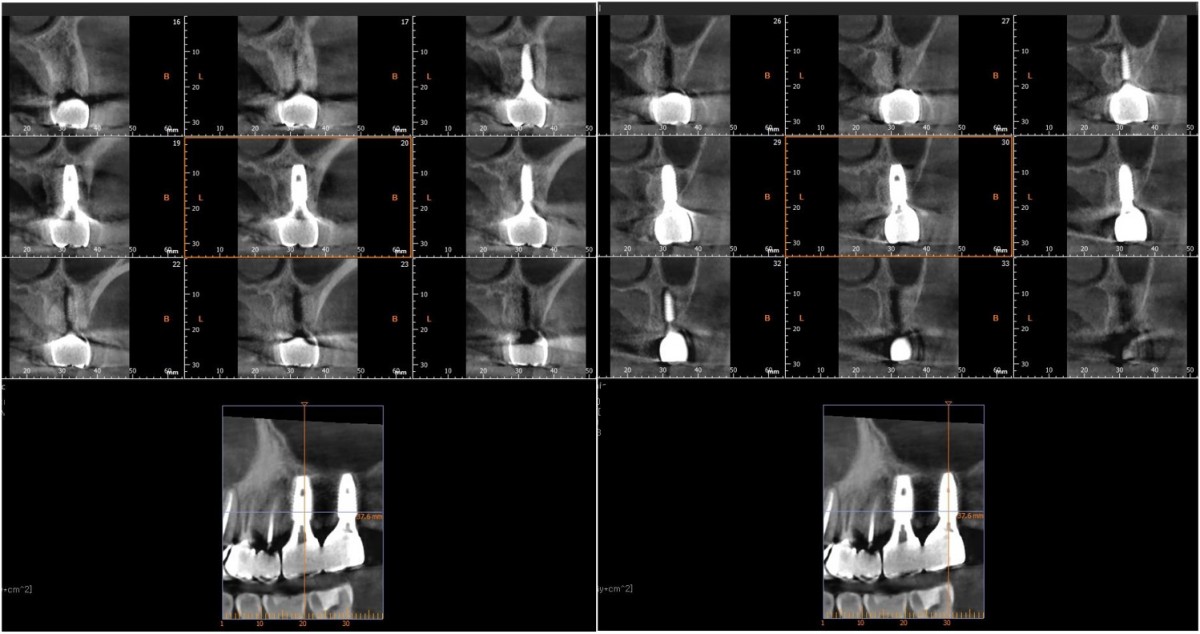

▲2 implants were placed. ArumDentistry NB1 5*10 (30Ncm) in the 1st molar and 5*10 (10Ncm) in the 2nd molar.

▲HA was inserted into the membrane with a hole in the middle and then inserted into the place where the Direction Pin was pulled out